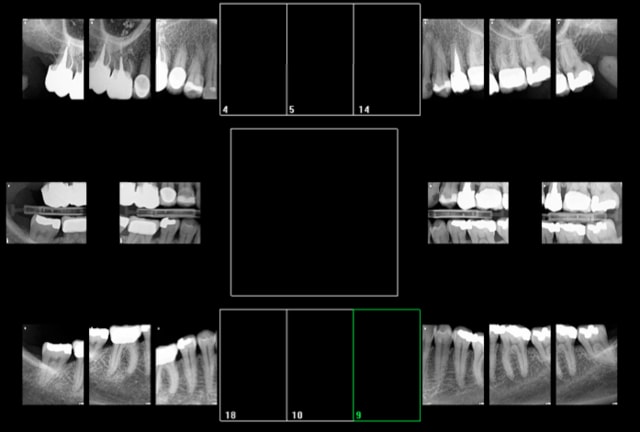

9 radios cita les pour moi

C'est ce que j'ai compté aussi Z54, au lieu de Z56. Un progrès. -)

comment cotez vous ca ?

5 radios côté pour moi

Les rétro alvéolaires du bas

1 rétro alvéolaire du haut

Et 2 rétro coronaires ( une droite et une gauche)

6 radios cotées pour moi : HBQK480

j'ai coté 17,14,24,27 36, 46